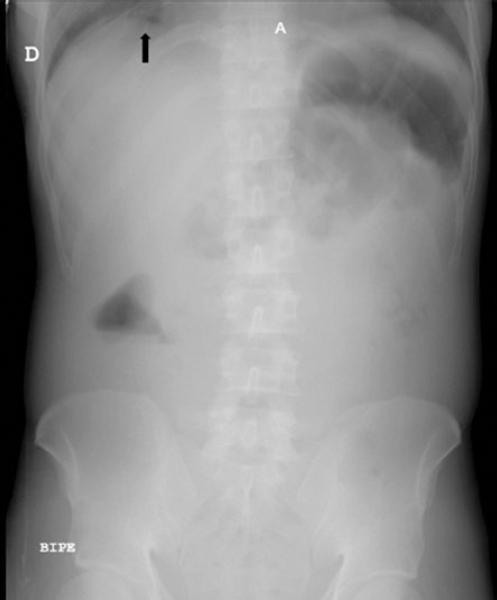

Varón de 44 años que acude a la urgencia de la E.S.E. Hospital Universitario del Caribe por un cuadro clínico de 18 horas de evolución, consistente en dolor abdominal tipo cólico asociado a dificultad para la micción y tenesmo rectal. El paciente refirió que en la madrugada sintió la necesidad de defecar y, al no conseguirlo, se introdujo por el ano un cuerpo extraño identificado como un trozo de madera o «palo» envuelto en plástico para de este modo lograr la defecación, retirándolo inmediatamente. Como antecedentes relevantes refirió consumo de cocaína (informó no estar drogado en el momento del acto). En la exploración física se evidencia abdomen blando, doloroso a la palpación generalizada, de predomino en flancos bilaterales, sin masas ni megalias, y sin signos de irritación, pero con presencia de defensa voluntaria. Se le realiza una radiografía abdominal que evidencia ausencia de aire distal (imagen sugestiva de neumoperitoneo) (Fig. 1), y una ecografía abdominal que revela líquido libre particulado, por lo que se decidió realizar cirugía laparoscópica exploratoria.

Figura 1 Radiografía de abdomen en la que se evidencia la ausencia de aire distal, lo que sugiere neumoperitoneo.